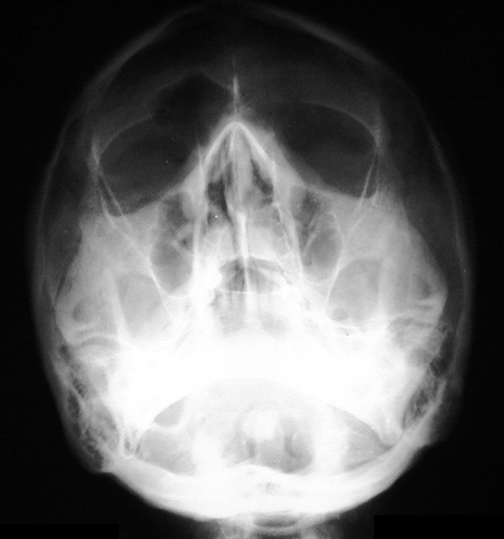

Identify the structures. Click the image for labeling.